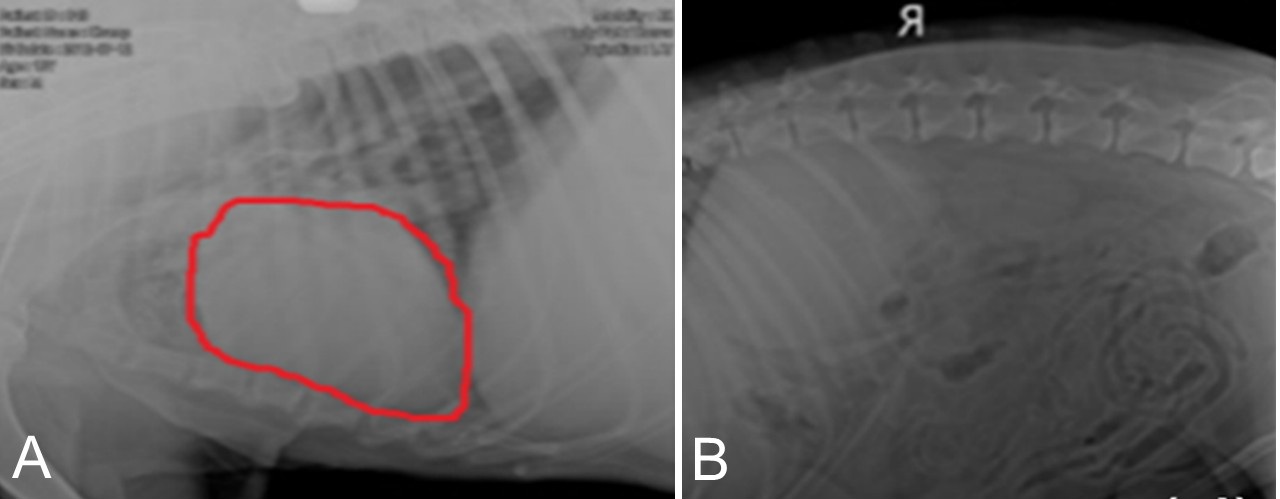

Multiorgan dysfunction in a geriatric dog with congestive heart failure complicated by chronic kidney disease and uremic enteritis